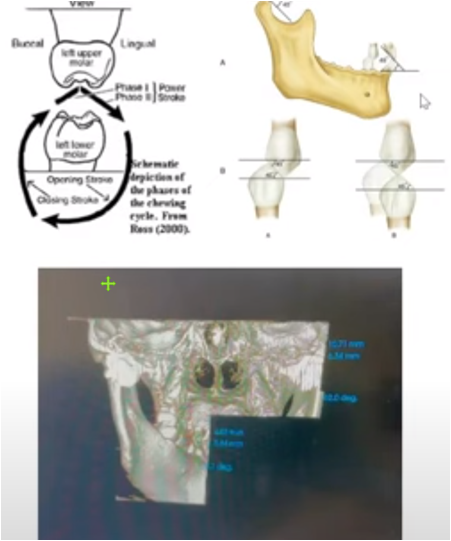

The COMiP two-stage correction system is a complete early correction system. In addition to aligning teeth and occlusal alignment, it can also correct muscle dysfunction, respiratory obstruction, help align teeth, and assist normal bone growth.

Introducing the COMiP two-stage system correction. Friends who need to watch it again or are curious can watch it on YouTube. Introduction to this course –

1. Why early correction is needed

2. Causes of occlusal abnormalities and bone growth deformities

3. Why are respiratory obstruction, allergies and occlusal abnormalities comorbid

4. Why do muscle dysfunction occur and how to complete the four corrections

COMiP two-stage early correction system. Our design has patents in many countries around the world. It is also the only system in the world that has four corrections. It is used in early correction. During the correction process, bone, teeth, muscle function and respiratory tract correction are gradually completed, providing a comprehensive solution. Problems with growing children. How to complete correction in two stages

There are many causes of malocclusion in early childhood. Heredity is usually the main cause. Other causes include trauma to the teeth, premature loss of deciduous teeth, and some bad oral habits (such as finger sucking, nail biting, lip biting, and tongue sticking out). Some mixed teeth Malocclusion in the orthodontic period can be treated early. The benefits of early treatment are to get rid of bad oral habits early, improve the appearance of the child, guide the permanent teeth to grow in the correct position, avoid the need for tooth extraction for correction in the future, or reduce the difficulty of correction in the future.

Orthodontic intervention must be dealt with in a timely manner. However, many parents do not know that bad habits such as mouth breathing and improper tongue positioning are also the main causes of children's irregular teeth. For example, "open bite" is mainly caused by children's bad habits. evolved.